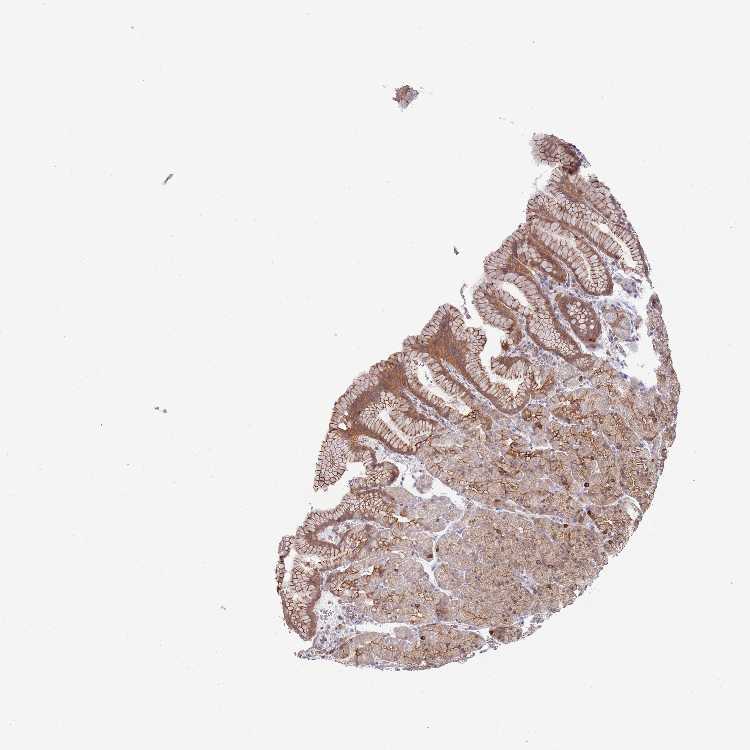

STOMACH - HPA RNA-seqi

The RNA-seq details section shows detailed information about the individual samples used for the transcript profiling and results of the RNA-seq analysis.

Information about each individual sample is listed below, including gender, age, a tissue section image and estimated fractions of cell types. nTPM (normalized transcripts per million) values give a quantification of the gene abundance which is comparable between different genes and samples.

Average nTPMi

Max subtype nTPM is the value for the subtype with the largest average nTPM across the subtype samples.

25.2

Female, age 33

Stomach sample 61

nTPM: 28

Cell types%

Glandular cells:

60

Smooth muscle cells:

5

Other cell types:

35